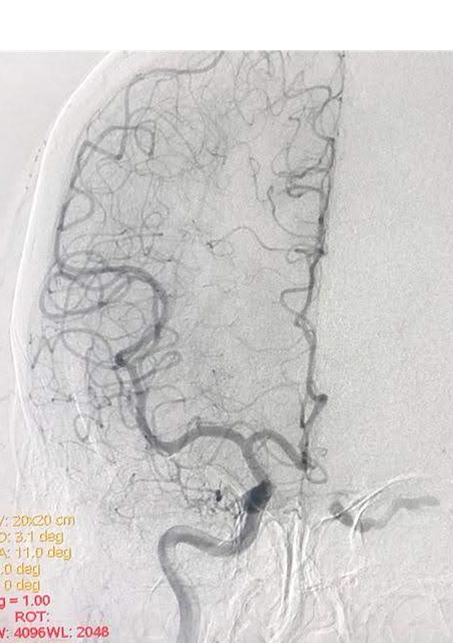

The DSA confirms the clinical diagnosis as well as the possible approaches to the cavernous sinus

My Endovascular Neurosurgeons & Interventional Neuro-radiologist colleagues usually cure this condition in an elegant way running the angio- catheter through the femoral vein and accessing the CCF through the Inferior Petrosal Vein. Although the inferior petrosal sinus is the simplest, shortest, and most commonly used venous route to the cavernous sinus, the superior ophthalmic vein (SOV), superior petrosal sinus, basilar plexus, and pterygoid plexus present other endovenous options.

In rare instances, the SOV is the sole route available as in this case. Hence I was called upon to expose the SOV for my colleagues to gain access to the CCF. Hence I was called upon to expose the SOV for my colleagues to gain access to the CCF.